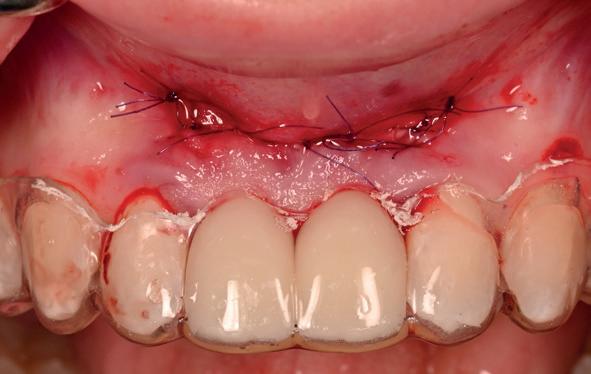

• Aanvulling zachte weefsels met de VISTA techniek en een vrij gingivatransplantaat uit het palatum links en direct dragen van de essix retainer

pincisies met hechtingen naar het buccale en coronale deel getrokken en aldaar ingehecht. Met twee incisies werd ook de emergence profile gecreëerd (afbeelding 6-13). Voor een goede genezing van het

11. Middels hechtingen het op de juiste plek trekken van het transplantaat

12. Transplantaat ingehecht

13. Occlusaal beeld verdikking van de zachte weefsels

14. Direct postoperatief plaatsen

van de essix met 2 dummy tanden